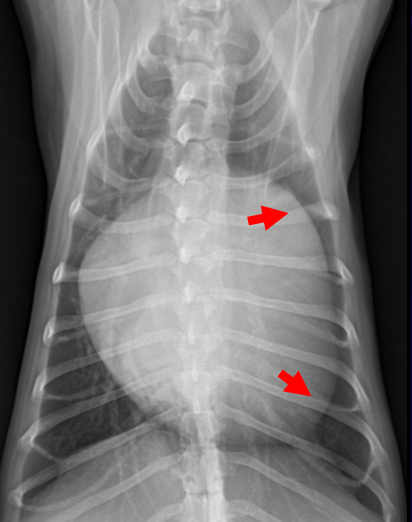

| 3기 (Severe : 좌심실까지 확실히 커짐) |

| 1) 좌심방-좌심실 경계가 사라지고 흉벽과 가까워짐 ⇒ 우심부전까지 발생. 2) Tracheal elevation도 매우 뚜렷. 3) 좌심실, 좌심방의 피가 완전히 섞여 와류가 생김 (Aliasing) 4) 기침, syncope, 폐수종까지 발생 |